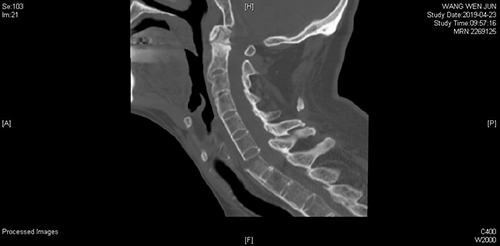

患者王先生,山东淄博市人,不慎摔伤后出现颈部疼痛,四肢放射痛及麻木感,颈部活动受限,四肢功能障碍,摔伤12天后入住山东省立医院脊柱外二科。脊柱外科丰荣杰等详细查看及分析患者的X线、CT、MRI影像学检查认为:患者C6双侧椎板骨折、C6-7椎体骨折脱位并椎管内血肿,C4-C5水平脊髓损伤,C4-T12水平硬膜外血肿,颈部软组织水肿,且患者患有强直性脊柱炎30余年。

手术前后影像学对照(术前C6双侧椎板骨折、C7椎体完全骨折脱位,术后达到解剖复位)